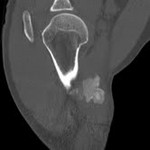

[画像診断]骨化性筋炎のCT画像 2010-04-12